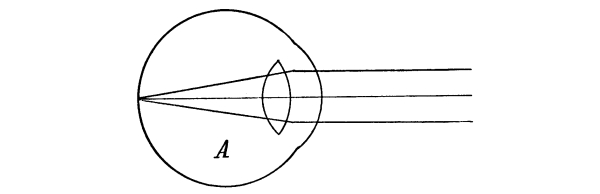

The Nose, 57—The Sense of Smell, 58—The Mouth, 59—The Hyoid Bone, 60—The Teeth, 60—The Sense of Taste, 61—Salivary Glands, 61—The Tonsils, 62—The Ear, 63—Eustachian Tubes, 63—Sensation of Hearing, 65—The Eye, 66—Lachrymal Gland, 68—Coats of the Eye, 68—Light Rays and Sight, 70—Accommodation, 72—Color Perception, 73. |